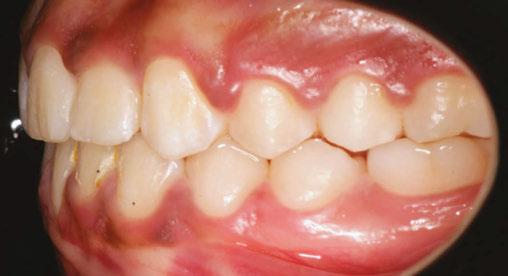

Figure 3: Initial right buccal

This case involves a 13-year-old female patient with a complex malocclusion that includes multiple dental and skeletal issues. During the initial consultation, clinical evaluation showed severe maxillary crowding along with generalized spacing in the mandibular arch. The patient’s occlusal relationships were asymmetric, with a Class I molar relationship on the right side and a Class II molar relationship on the left. Notably, an anterior crossbite was observed, further complicated by a narrow, V-shaped maxillary arch — a common presentation that often exacerbates anterior-posterior discrepancies and limits functional occlusion. The patient also demonstrated poor oral hygiene, which is a key indicator of an indirect bonding system that does not reduce excess flash. ODB is superior in flash reduction, by being able to remove excess adhesive from three sides of the bracket instead of competitors who only remove adhesive from one side of the bracket. The presence of adhesive around brackets contributes to surface roughness which leads to plaque accumulation.1 Flash reduction will be very important for every patient’s orthodontic success (Figures 1-3).